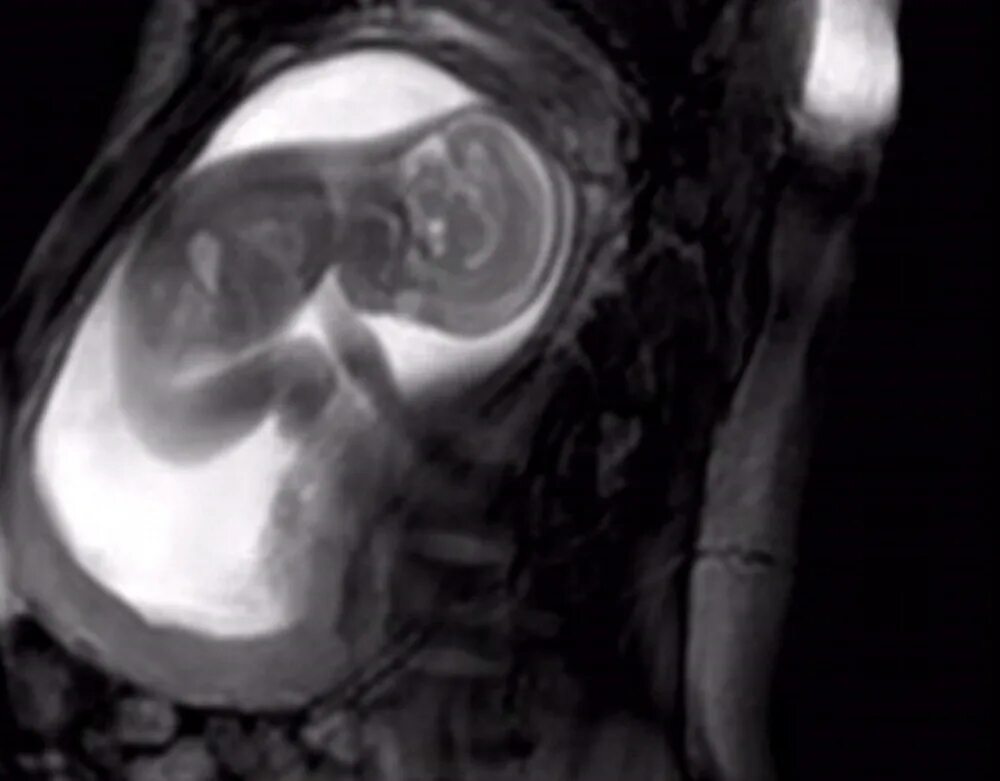

Мрт беременной